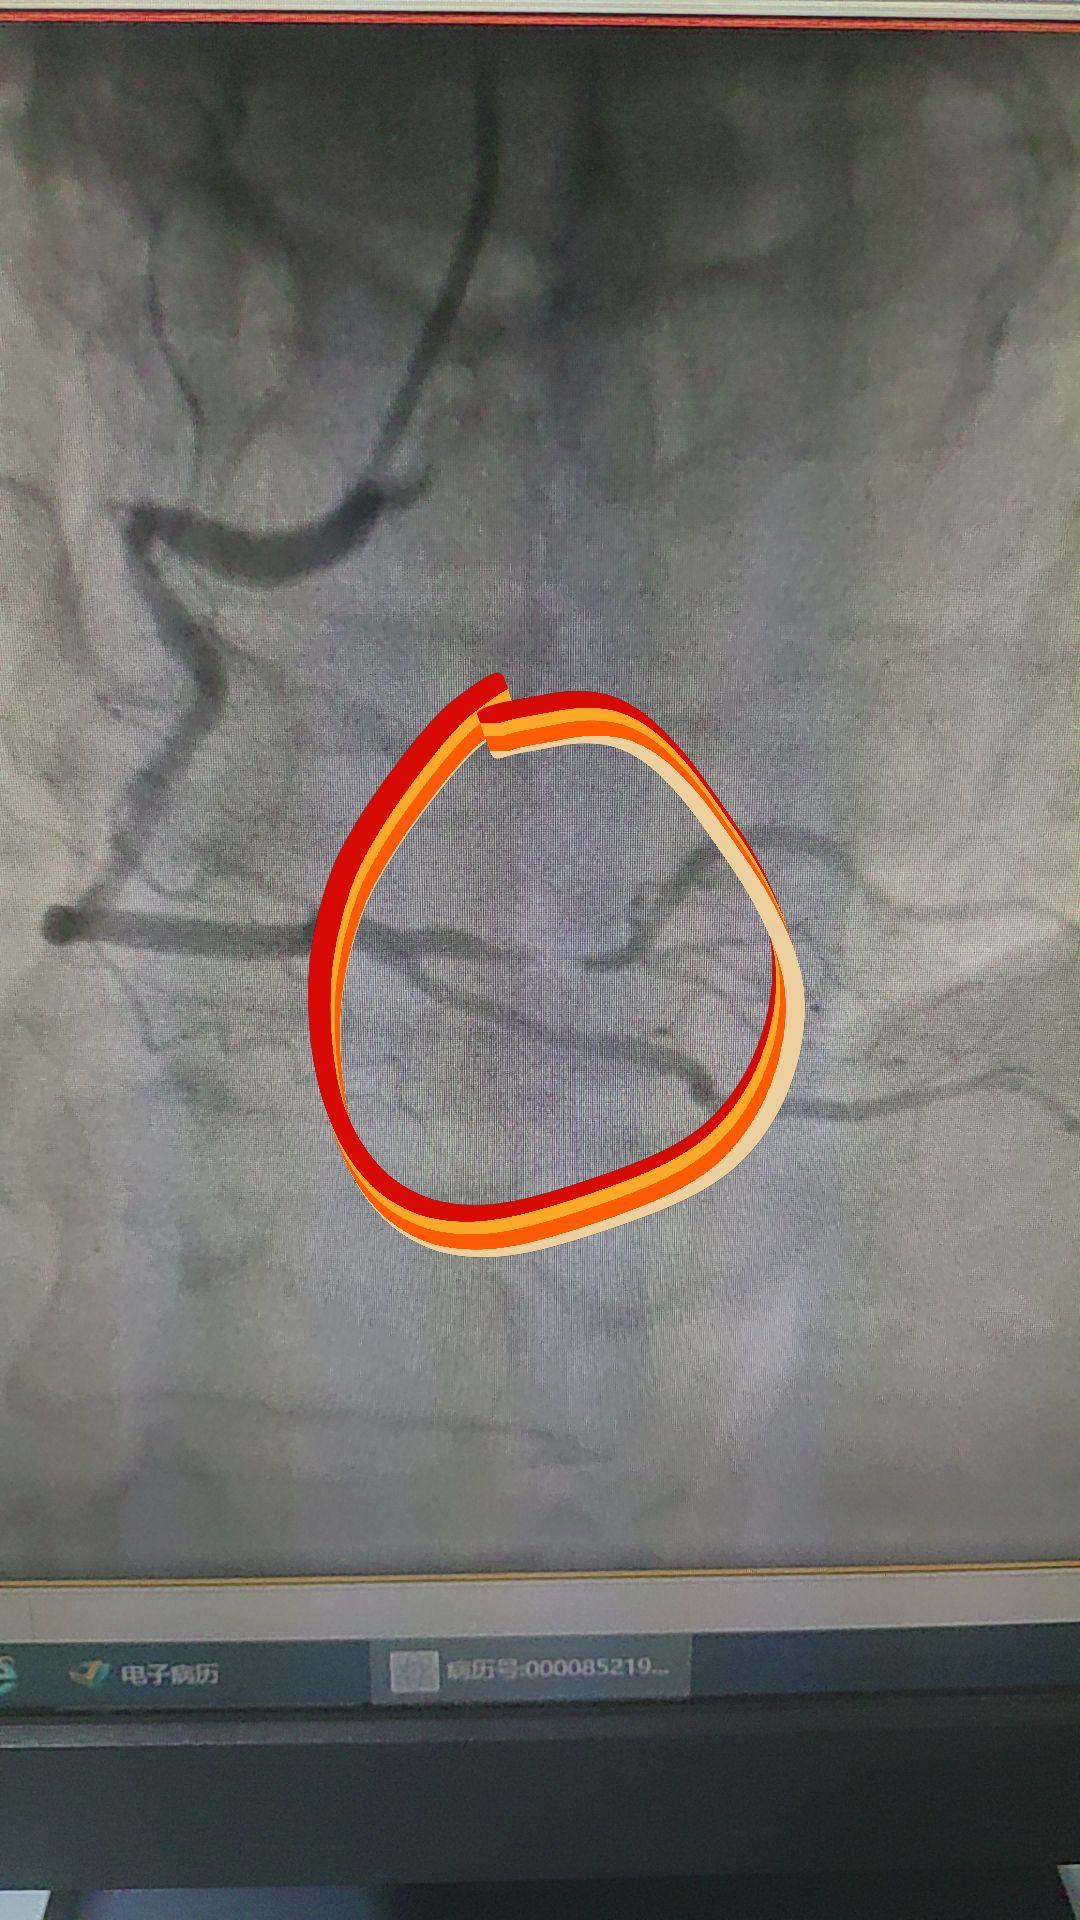

今天的手术遇到三个小困难: ①桡动脉痉挛更改入路 ②腹主动脉严重迂曲增...